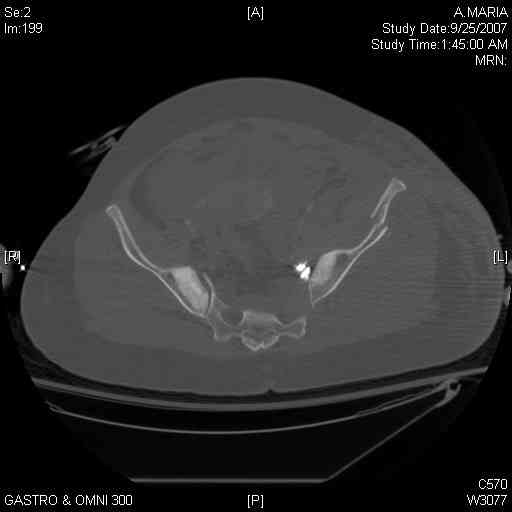

[Ortho] comminuted crescent fx

40 ish female ejected from car. Unstable, DPL negative, went to angio and had her pelvic bleeds embolized after many units of blood. GCS 6, floating elbow, clavicle, bothbones, etc.

My standard approach to  this pelvis would be posterior, reduce/lag/plate  thecrest, reduce/plate the caudal extent on the posterior crest and 1-2 lags back to front. In this case, the crest comminution seems to make plating all

the way to the ASIS useless, as the plate would be on free floating fragments. Would plating the posterior extent of the fracture to secure the

reduction at the SI joint and 2 screws back to front be sufficient fixation? Would anyone do a perc reduction and perc back to front screws, and would that be sufficient if the SI joint could be reduced (although I don't see how this could be accurately reduced closed). Would an ilioninguinal with a pelvic brim plate and posterior column screws be a better approach, although reducing the SI would be more indirect and less accurate?